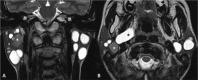

Inflammatory and obstructive disorders of the salivary glands are caused by very different pathological conditions affecting the gland tissue and/or the excretory system. The clinical setting is essential to address the appropriate diagnostic imaging work-up. According to history and physical examination, four main clinical scenarios can be recognised: (1) acute generalised swelling of major salivary glands; (2) acute swelling of a single major salivary gland; (3) chronic generalised swelling of major salivary glands, associated or not with "dry mouth"; (4) chronic or prolonged swelling of a single major salivary gland. The algorithm for imaging salivary glands depends on the scenario with which the patient presents to the clinician. Imaging is essential to confirm clinical diagnosis, define the extent of the disease and identify complications. Imaging techniques include ultrasound (US), computed tomography (CT) and magnetic resonance (MR) with MR sialography.